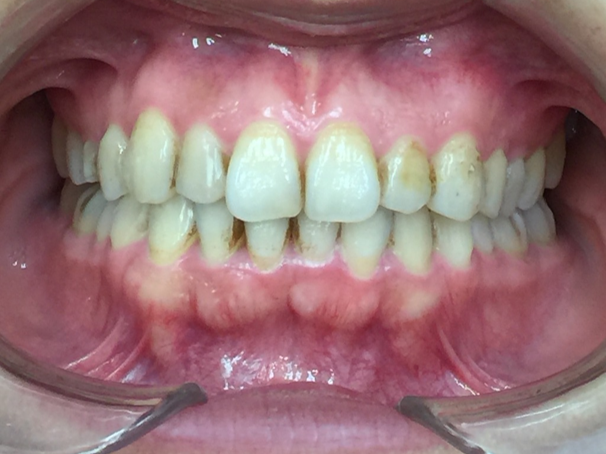

20代女性「オンライン授業中に映る自分の口元が気になる」歯が重なり合ってデコボコしている歯並びをマウスピース型矯正「インビサラインフル」により歯を抜かずきれいに整えた症例

上下前歯が正しい位置に並び、きれいに整いました。

患者様も、以前は笑うときに口元を隠すなど気にしておられましたが、現在は笑顔でお話しされるようになりました。